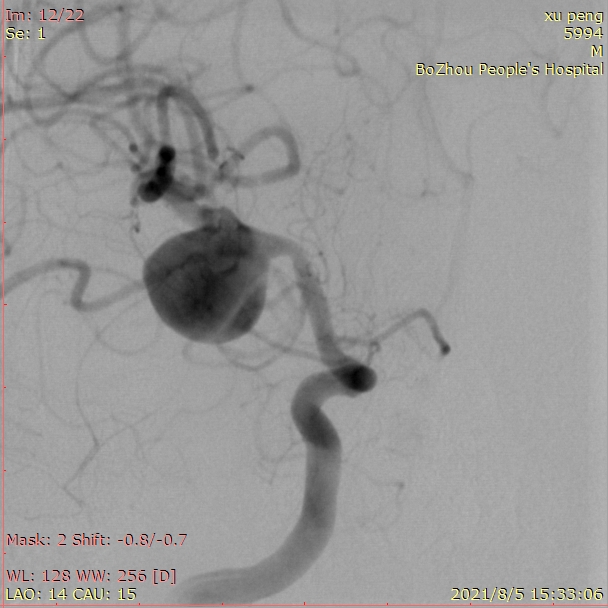

5、急诊查CTA提示:右侧大脑中动脉M1段巨大动脉瘤,和患者家人沟通后送导管室急诊造影。

右侧颈内动脉正位造影

右侧颈内动脉侧位造影

三维重建提示:右侧大脑中动脉M1段巨大动脉瘤,15.4mm*13.3mm大小,瘤颈7.1mm,近似球形,瘤顶指向下方。